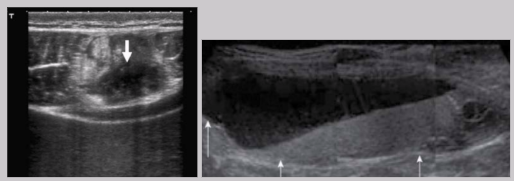

Acute phase of foreign body

Foreign body present < 3 days

Immediately after injury → air or dirty shadowing

24 hrs after injury → hypoechoic ring/halo develops

Intermediate phase of foreign body

Foreign body present 3 - 10 days

Fluid replaces air

Most pronounced hypoechoic halo

Chronic phase of foreign body

Foreign body present > 10 days

Dense granular material develops around FB

Inflammatory response → clean shadowing similar to bone